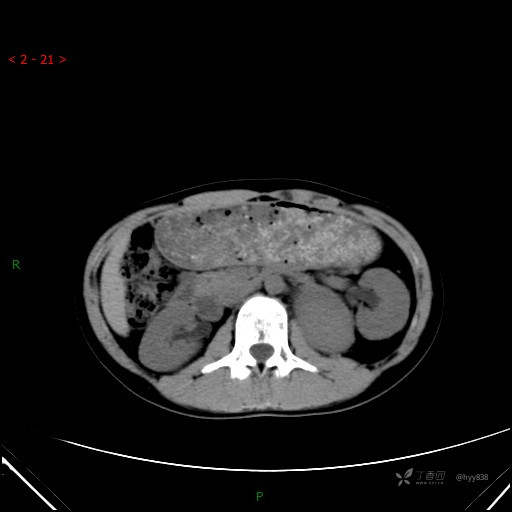

增强动脉期